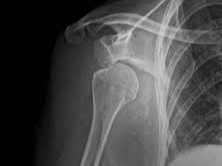

어깨 관절은 팔뼈(상완골), 견갑골, 쇄골 등 세 가지 주요 뼈와 이를 연결하는 근육, 힘줄, 인대 등으로 구성되어 있습니다. 특히 ‘회전근개(rotator cuff)’라고 불리는 네 개의 근육은 어깨의 회전과 안정성 유지에 중요한 역할을 합니다. 문제는 이 구조가 매우 유연하면서도 섬세하다는 점입니다. 작은 외상이나 반복적인 사용만으로도 손상이 일어나기 쉽습니다.

🔸 회전근개 질환

회전근개에 염증이 생기거나, 퇴행성 변화로 인해 파열되는 경우입니다. 팔을 들거나 뒤로 돌릴 때 통증이 심해집니다.